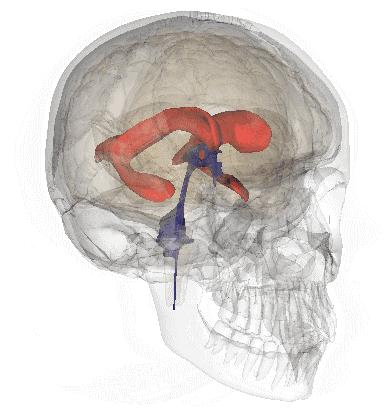

大脑供血动脉3D扫描CT成像

磁共振成像&人脑模型对比